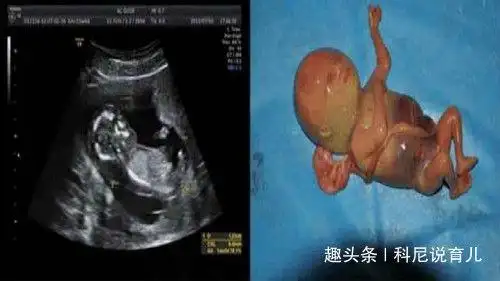

胎儿5个月查出畸形孩子被引产后老公直奔公司怒砸老板办公室